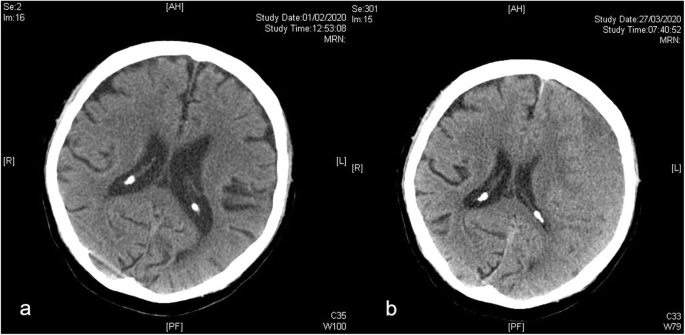

Since March 2020, we have observed a pattern of delay in the presentation of chronic subdural haematoma patients after their initial head injury during this period of lockdown (Figs. 1, 2 and 3). The figures illustrated patients who had minor head injuries in January or February 2020. Their initial CT scan of the brain at the time of injury showed no major intracranial haemorrhage (Figs. 1, 2 and 3a). They went home with medical advice. Subsequently, they gradually deteriorated with non-specific symptoms including unsteady gait, dizziness, or clumsiness. They initially avoided attending the hospital or clinic due to the COVID-19 pandemic. Finally, at around 7 to 10 weeks after their initial minor head injury (Figs. 1, 2 and 3b), they were diagnosed with cSDH. In our tertiary neurosurgical centre, this delay pattern was not observed in other major neurosurgical conditions including ruptured aneurysms, stroke, or spinal cord injury during this lockdown period.

a CT brain scan of an 86-year-old gentleman at the time of injury. He had a minor head injury due to postural hypotension and his anti-hypertensive medication was titrated. CT scan initially showed no intracranial hemorrhage and he was discharged with medical advice. He subsequently had a gradual onset of worsening dizziness. b He presented to the hospital 7 weeks and 5 days after his initial minor head injury. The new CT showed a newly diagnosed left-sided chronic subdural hematoma with mass effect and midline shift. He had a good recovery after emergency burr hole drainage